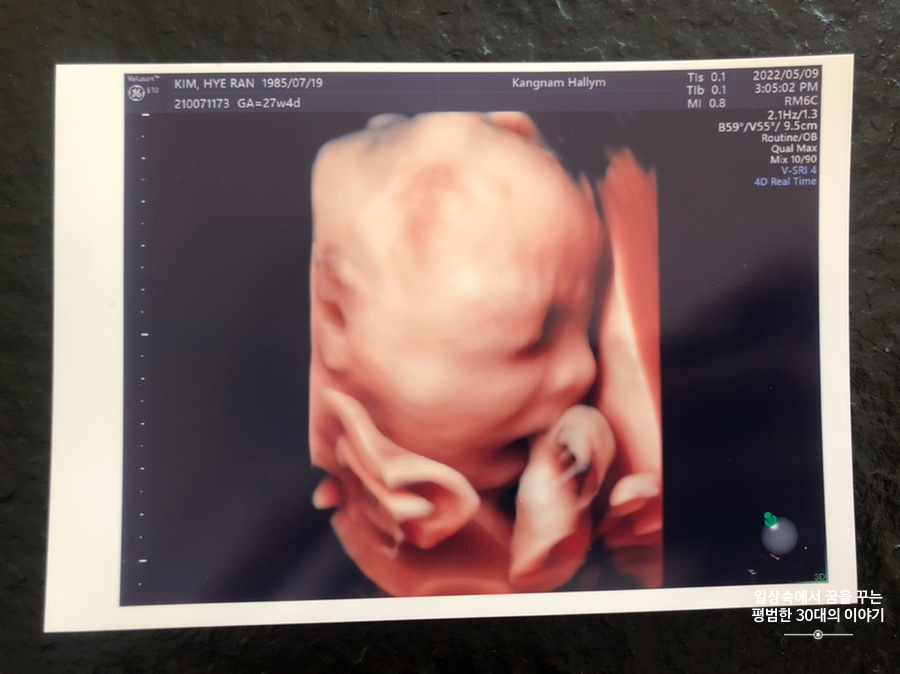

오늘은 입체 초음파 보는 날!!! 입체 초음파는 처음인데다 3주 만에 이안이 얼굴을 본다 생각하니 무척 설레는 마음으로 병원에 갔다. 첫 번째 시도에서는 계속 내 등 쪽으로 얼굴을 대고 엎드려 있어 실패! 초코우유 먹고 열심히 걸은 후, 30분 뒤에 다시 진행한 두 번째 시도에서는 얼굴 반쪽을 보여줬다. 얼굴 전면을 보지 못해 너무 아쉬웠지만 그래도 손가락 빨고 있는 모습, 웃고 있는 모습, 입 뻐끔 거리는 모습, 발차기 하는 모습, 손가락 쥐었다 폈다 하는 모습, 손을 휘적휘적 거리는 모습 등 다양한 모습을 보여줘서 그것만으로도 충분히 만족스러웠다. 내가 다니고 있는 강남성심병원은 입체 초음파가 다른 병원에 비해 무척 비싼 편인데(진료비 내역을 보니 초음파 진단료가 129800원 나옴) 그나마 위안을 삼을 수 있는 것은 화질이 그나마 좋은 편이라는 것이다.